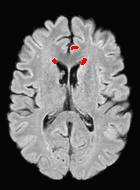

We observed that memberships predicted with an FC layer result in more false positives compared to a fully convolutional network. An example is shown in Fig. 2, where lesion memberships are generated from MPRAGE and FLAIR using the proposed model of convolutional pathways and a comparable model where the last convolutional pathway after concatenation (see Fig. 1) is replaced with a FC layer predicting voxel-wise memberships. The membership image generated with an FC layer, although being close to inside the lesions, has high values () in the left and right frontal cortex where the FLAIR image shows some artifacts. However, the membership obtained with the proposed method shows relatively low values near the frontal cortex.

Patch size is another important parameter of the network. In computer vision applications such as object detection, usually a whole 2D image is used as a feature. However, full 3D medical images can not typically be used because of memory limitations. Fig. 4 shows examples of lesion memberships obtained with different sized 2D patches. As the patch sizes increases, the false positives that are mostly observed in the cortex tend to decrease. Fig. 5 shows a plot of Dice and LFPR with various patch sizes, ordered from left to right according to their increasing size. Note that smaller patches ( to ) produced significantly lower Dice and higher LFPR compared to other patches (), as seen from the memberships in Fig. 4. Also some of the highest Dice and lowest LFPR were observed for patches with large in-plane size, i.e., , , and . It was observed in Fig. 5 that there is no significant difference between Dice coefficients for , , or , but LFPR of both and are significantly lower than that of (). We chose as the optimal patch size. Other choices of smaller and patches (not shown) yielded worse results. Note that although training was performed with different patch sizes, the memberships were generated slice by slice, as the trained model consisted only of convolutions and did not need any information about patch sizes.

In our experiments, we used large 2D patches similar to Ghafoorian et al. (2017b), in comparison to isotropic 3D patches as used before, e.g., in Valverde et al. (2017), in Wachinger et al. (2017), and in Kamnitsas et al. (2017). The rationale behind using large anisotropic patches is twofold. First, experiments with full 3D isotropic or patches showed little or no improvement in Dice and led to increased false positives, with memberships similar to the one with patches, as shown in Fig. 4. Larger isotropic patches, e.g. or , showed inferior segmentation, and in some cases, optimization did not converge. The reason is that the FLAIR images in the test datasets had inherently low resolution in the inferior-superior direction, mm and mm compared to in-plane resolution of mm. Therefore 2D axial patches capture the high resolution in-plane information that represents the original thick axial slices. Second, the lesions are usually focal and small in size, unlike other brain structures. Therefore a very large isotropic patch around a small lesion can include superfluous information about the lesion, which can increase the amount of false positives. Note that with in more recent studies employing high resolution 3D FLAIR sequences, it is trivial to extend the algorithm to accommodate for 3D patches.